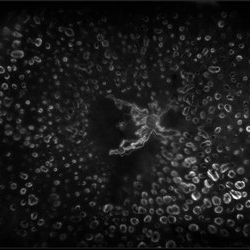

Color fundus montage of an 12-year-old boy with ocular parasitosis affecting his left eye. Patient presented with decreased vision and recent travel to Florida. The specimen was lost in the lab and was never recovered.

Photographer: Olivia Rainey

Imaging device: Topcon 50dx

Condition/keywords: color fundus photograph, color photo, intraocular foreign body, left eye, montage, parasite